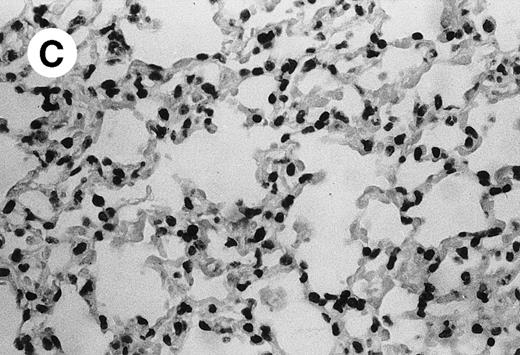

Histopathology of the MWReg30-induced reaction.

IV injection of MWReg30 caused within 15 minutes a peripheral vasodilatation, as evidenced by red extremities (tail and feet) and uncoordinated movements. These signs persisted for 60 to 90 minutes. Proportional to the injected dose of MWReg30, mice showed intestinal hemorrhages, ruffled fur, and reduced flow rate during blood sampling. Lung, kidney, and liver were sampled at different times after MWReg30 injection for histological examination. Histopathology of the whole lung performed 60 minutes after injection showed enhanced thickness of alveolar septa, due to edema and to increased cellularity, consisting of polymorphonuclear and mononuclear cell accumulation in capillaries, as compared with lungs from mice injected with PBS (Fig 4) or control IgG (not shown). This change was found to be uniform, not focal, in the two lungs (n = 6). After 24 hours, lungs showed a further enhancement of septa thickness, due to mononuclear, but not polymorphonuclear, cell accumulation in capillaries and interstitium, as well as plasma leakage into the alveolar space (Fig 4C). No changes were observed in peribronchiolar areas. As early as 20 minutes after IV injection, semithin sections showed that the vascular engorgement was essentially due to red blood cells, with very few leukocytes or platelets (Fig 4D). Twenty-four hours after injection, some mice showed centrolobular necrosis in the liver as well as glomerular shrinkage and enlargement of Bowman spaces in the kidney, compatible with hemodynamic changes of shock, but without evidence of acute tubular necrosis. Thrombi or microthrombi were not seen in any of the examined organs. Platelets recovered from the blood of mice 30 minutes after injection of MWReg30 did not express P-selectin as determined by FACS analysis. In sera from mice obtained 90 minutes after injection of MWReg30, no TNF was detectable.

Lung histopathology. Aspect of alveolar walls 60 minutes after IV injection of PBS (A) or 10 μg of MWReg30 (B); (C) 24 hours after IV injection of 10 μg of MWReg30; (D) vascular engorgement of septal capillaries with erythrocytes, 20 minutes after IV injection of 100 μg of MWReg30. (A through C) Hematoxylin/eosin staining of paraffin-embedded section (original magnification × 400). (D) Toluidine blue staining of Epoxy resin-embedded sections (original magnification × 1,000).

The lung congestion, as well as the increased cellularity of the lung septa, due to mononuclear and polymorphonuclear cells, are akin to LPS-induced lung pathology. The vascular engorgement, essentially due to erythrocytes, was more pronounced than in mice injected with 1,000 μg LPS (not shown). Histological examination showed that these changes were neither focal nor associated with atelectasis: the increased cellularity was uniform and was observed in both lungs. In contrast, control lungs from mice injected either with PBS or with normal IgG were consistently free of accumulated cells in the septa. In MWReg30-injected animals, the increased cellularity appeared to be due to cell accumulation in both vascular and interstitial compartments, although electron microscopic studies are required to clarify this point. Preliminary studies show enrichment of pinocytotic vesicles (Männel et al, manuscript in preparation). Altogether, the picture is compatible with the very early steps of acute lung injury.